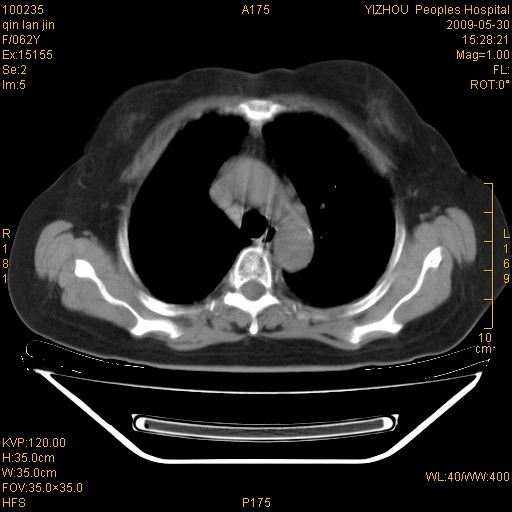

标题: CT20268:肺泡癌?间质性肺炎? [打印本页]

标题: CT20268:肺泡癌?间质性肺炎?

女,62岁,近二年经常咳嗽,近二个月,消瘦、乏力。

两肺弥漫性间质性病变(间质性肺炎伴肺间质纤维化?)。

间质性肺炎伴肺间质纤维化。

纵隔淋巴结大,须排外癌性淋巴管炎